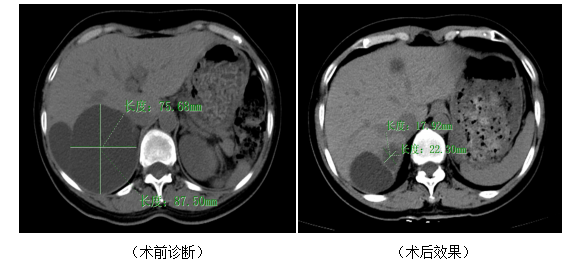

体检报告上突然跳出 “肝囊肿”“肾囊肿”!先别紧张!这些长在肝、肾上的 “小水泡”,其实大多是良性的—就像脏器里裹着清亮液体的小囊袋,一般不会癌变。但当它们长到直径超过 5 厘米,就可能开始 “捣乱”:比如压得肚子胀、腰背痛,甚至引发感染出血。这时候,介入微创治疗就能轻松解决问题啦! 肝、肾囊肿长啥样? 你看,囊肿就像挂在肝脏上的 “透明小水囊”,外面一层薄薄的囊壁,里面装着澄清的液体(少数会有点浑浊)。小的囊肿(直径<5 厘米)通常安安静静,不用特殊处理;但大囊肿(直径>5 厘米)会像气球一样越鼓越大,压迫周围组织,让人不舒服。 介入治疗:“小针眼” 解决大问题科 传统开刀手术要划口子、缝针,恢复慢还留疤。现在的介入治疗就不一样了,全程就像 “给囊肿做个微创手术清洁”,局部麻醉下就能完成,患者全程清醒不遭罪。 1、精准定位:医生用超声或 CT 当 “透视眼”(屏幕上能清楚看到囊肿的位置、大小,还有周围的血管和脏器),就像给穿刺 “导航”,绝不会乱扎。 2、微创穿刺:一根比输液针略粗的细针,在影像引导下轻轻扎进囊肿中心,巧妙避开重要组织,伤口只有针眼那么大。 3、抽光 “囊液”:用注射器把囊肿里的液体慢慢抽干净,原本鼓鼓的囊肿会立刻瘪下去,压迫感瞬间减轻。 4、“封死” 囊腔:往空了的囊肿里注入一点点无水酒精(专业叫 “硬化剂”),它能让囊壁的细胞失去 “分泌液体” 的功能,就像给囊壁 “粘上口子”,以后再也不会积水啦。 5、拔针收尾:抽掉细针,穿刺点贴个小敷贴就行,连缝针都不用,几乎看不见伤口。 为啥大家都选介入治疗?4大优势说清楚 简单说,介入治疗的好处用一句话总结:“小创伤解决大问题,恢复快还不咋花钱”!尤其适合年纪大、有高血压糖尿病等基础病,没法耐受手术的病人。 最后再说几句 1、不是所有囊肿都要治:如果囊肿直径<5 厘米,没不舒服,每年做次超声复查就行(就像给囊肿 “拍照片” 跟踪大小)。 2、找对医生很重要:一定要选经验丰富的介入放射科医生,他们用影像 “导航” 更精准,风险更低。 3、术后别大意:治疗后可能有点轻微腹痛或低热,这是硬化剂在起作用,一般几小时就好,不用紧张。但如果疼得厉害或发烧超过 38.5℃,要及时告诉医生。 4、定期复查不能少:术后间隔3个月、6个月、1年要做超声复查,确认囊肿没再变大。